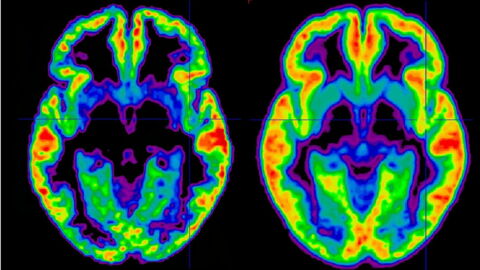

If left untreated, lupus can lead to complications such as inflammation. This can affect other parts of the body, such as the kidneys, central nervous system, and heart. Most complications usually occur a few years after the initial diagnosis.

If lupus reaches the kidneys or nervous system, immunosuppressants are prescribed in order to chemically suppress the effects of the immune system. All of these medications are effective in the treatment of lupus, but some have significant side effects. This is why it's important to have regular follow-ups with a specialist.